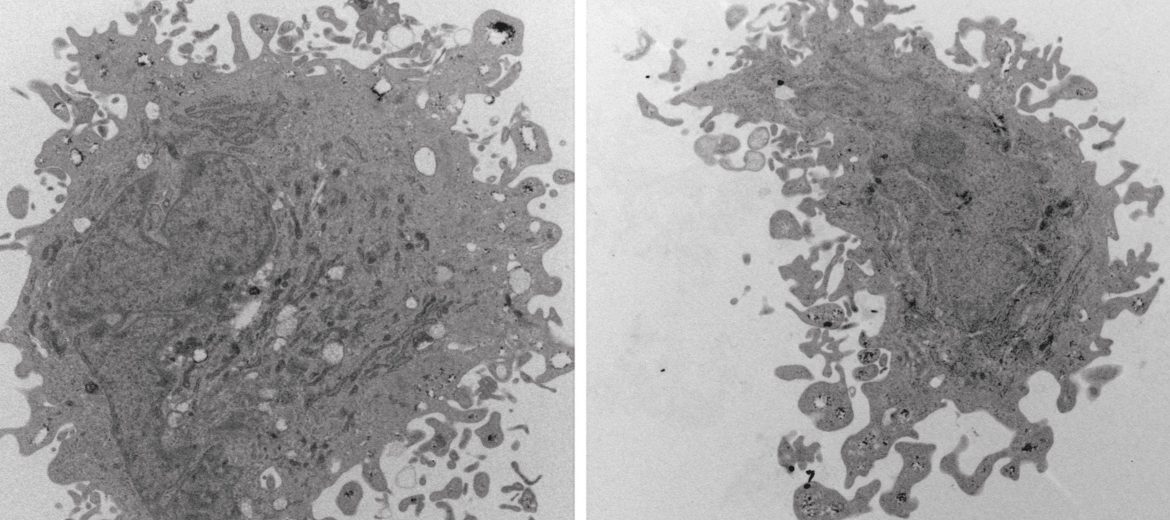

She has been using the AMMRF (now Microscopy Australia) at the University of Adelaide to look at the fine detail of the cells’ structure by using transmission electron microscopy. DPSCs from different age groups showed no obvious structural differences. All the cells showed well-defined, irregularly shaped nuclei, endoplasmic reticulum and membrane projections on the outer membrane. Electron microscopy is combining with functional data to provide a thorough comparison of the differentaged stem cells.

Together they are helping to bring stroke treatment with a patient’s own stem cells a step closer.